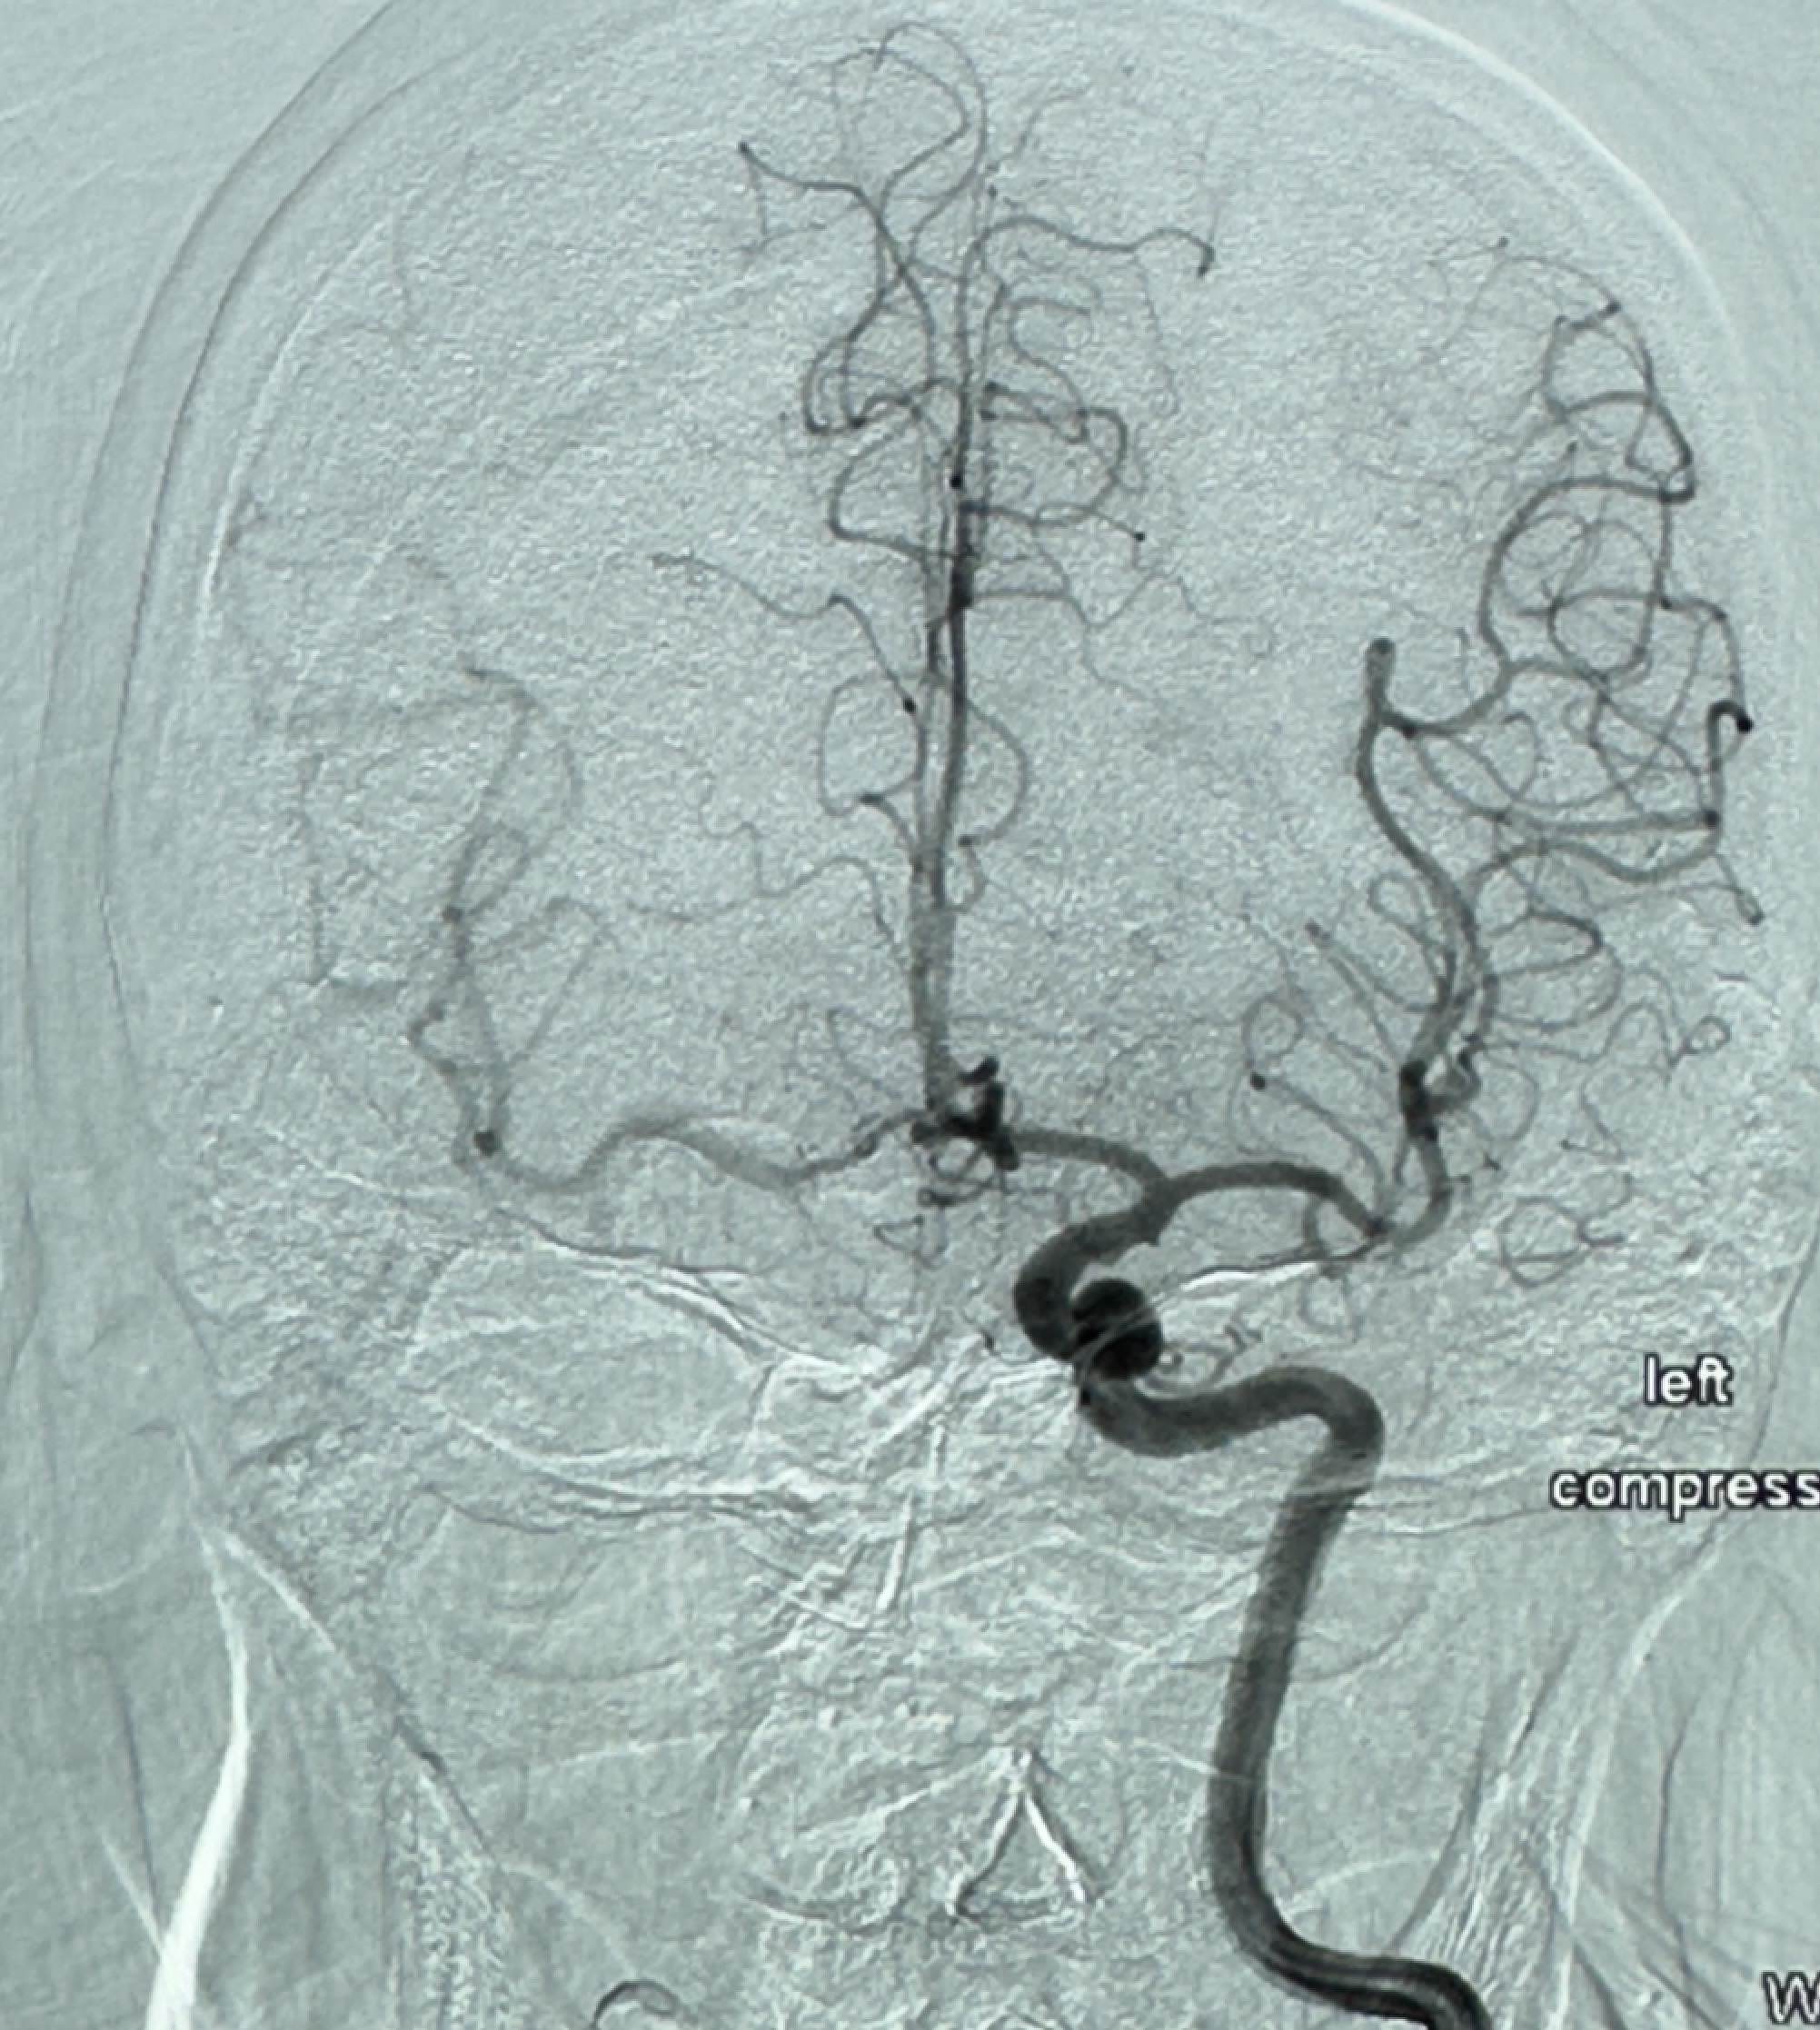

2023-12-08 复旦大学附属华山医院 全脑血管造影:右侧颈内动脉C6段动脉瘤,瘤颈6.68mm,动脉瘤大小13.28*12.34mm

2023-12-08外院DSA:右侧颈眼动脉瘤,约13*12mm大小,压颈试验显示左右向及后向前代偿可